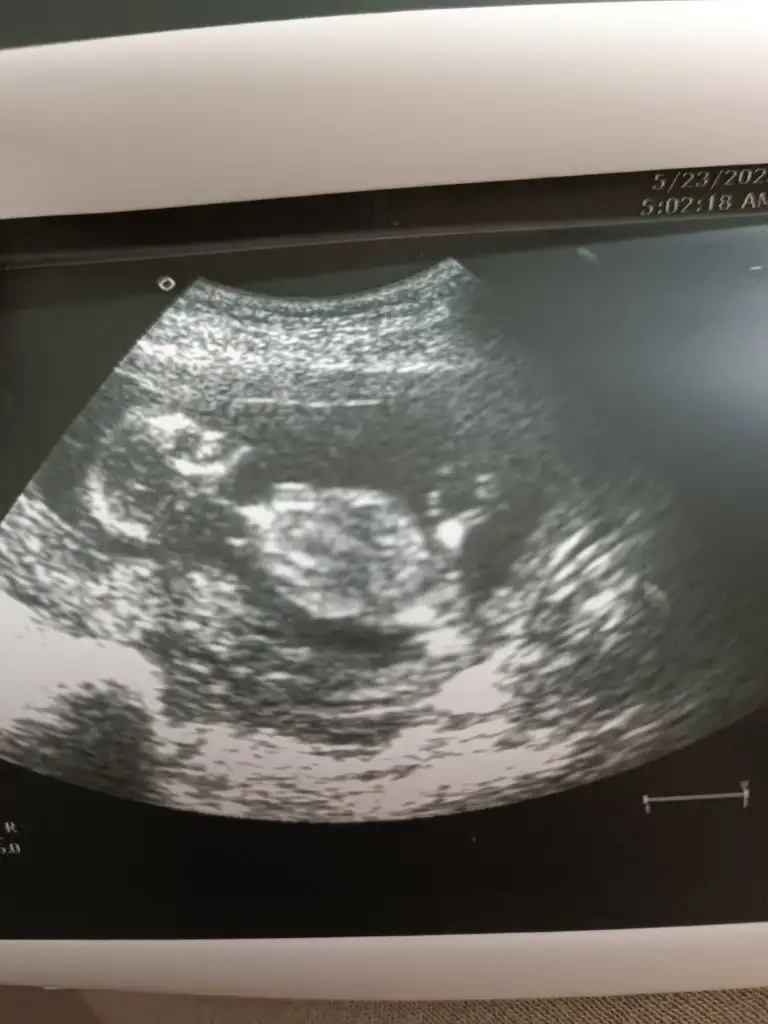

Evet benimde karından ölçtü doktora göre sorun yok 3.25 mm dedi 16 haftalık ama internette 40mm gilen yazıyor biraz tedirgin oldumBizim doktorumuz her kontrolde ölçüyor düşük tehditi olabilir mi diye ölçüm sonucunu hiç öğrenmedim fakat doktor sorun yok rahat olabilirsin dedi her seferinde vajinal ya da karından yapılabiliyor diye biliyorum bizimki karından baktı en son keseden rahim ağzına kadar olan yeri ölçüyor

Ben her gittiğimde bakıyor ultrason ile. Bu gebeliğimde biraz temkinliyim daha önce bi kaybım olduğu için belki o yüzden hassas davranıyor gerekli mi bu haftada bilemiyorum. En son 14 haftalık gittiğimde 6 cm di. Çok iyi demiştiKızlar konuyu takip ediyorum ama gözden kaçırmış olabilirim rahim ağzı uzunluğu öümü yaptıran varmı sonuçlarınız nasıl geldi doktor nasıl yorum yaptı

Nasııl bişey bu biliyomusun ultrasonda bebek varya karından tabi onun altında bi bölgeye uzunluğa bakıyor bebek boyunu ölçer gibi vajinal falan değil biri 33 biri 35 geldi sonucumda kızımda hatırlamıyorum ama ikizlerimde 2 ayrı doktor bakarken farkettim benKızlar konuyu takip ediyorum ama gözden kaçırmış olabilirim rahim ağzı uzunluğu öümü yaptıran varmı sonuçlarınız nasıl geldi doktor nasıl yorum yaptı